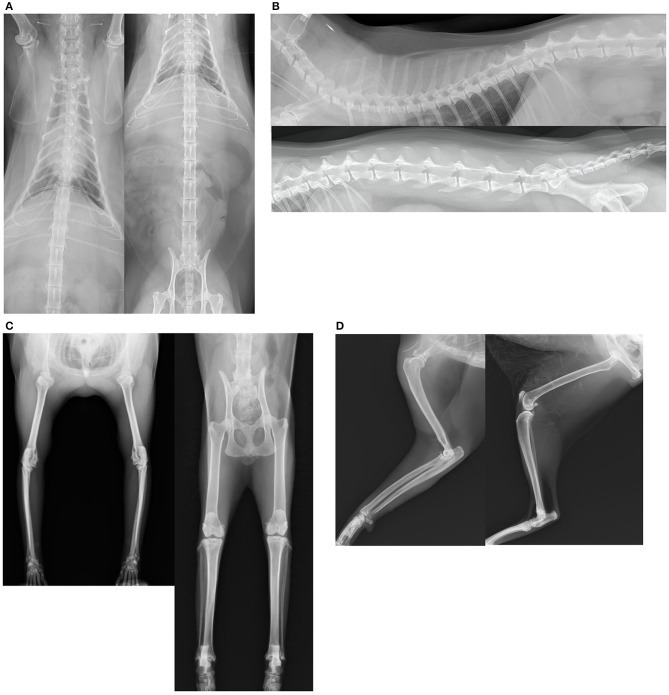

고양이 중 약 40%가 관절염 증상을 보이고, 12살 이상은 90%가 관절문제를 보인다. 고양이는 개보다 다관절을 많이 사용하는데 절뚝거리기 보다는 활동이나 보폭이 줄어드는 경향이 있다. 그렇지만 벗스버그 박사는 방사선검진에서 관절염 징후가 있는 고양이는 고통을 느끼지 않더라도 치료해야 한다고 강조한다. 고통을 줄이고, 관절기능을 개선하고, 관절염 악화를 지연시키는 목적이다.